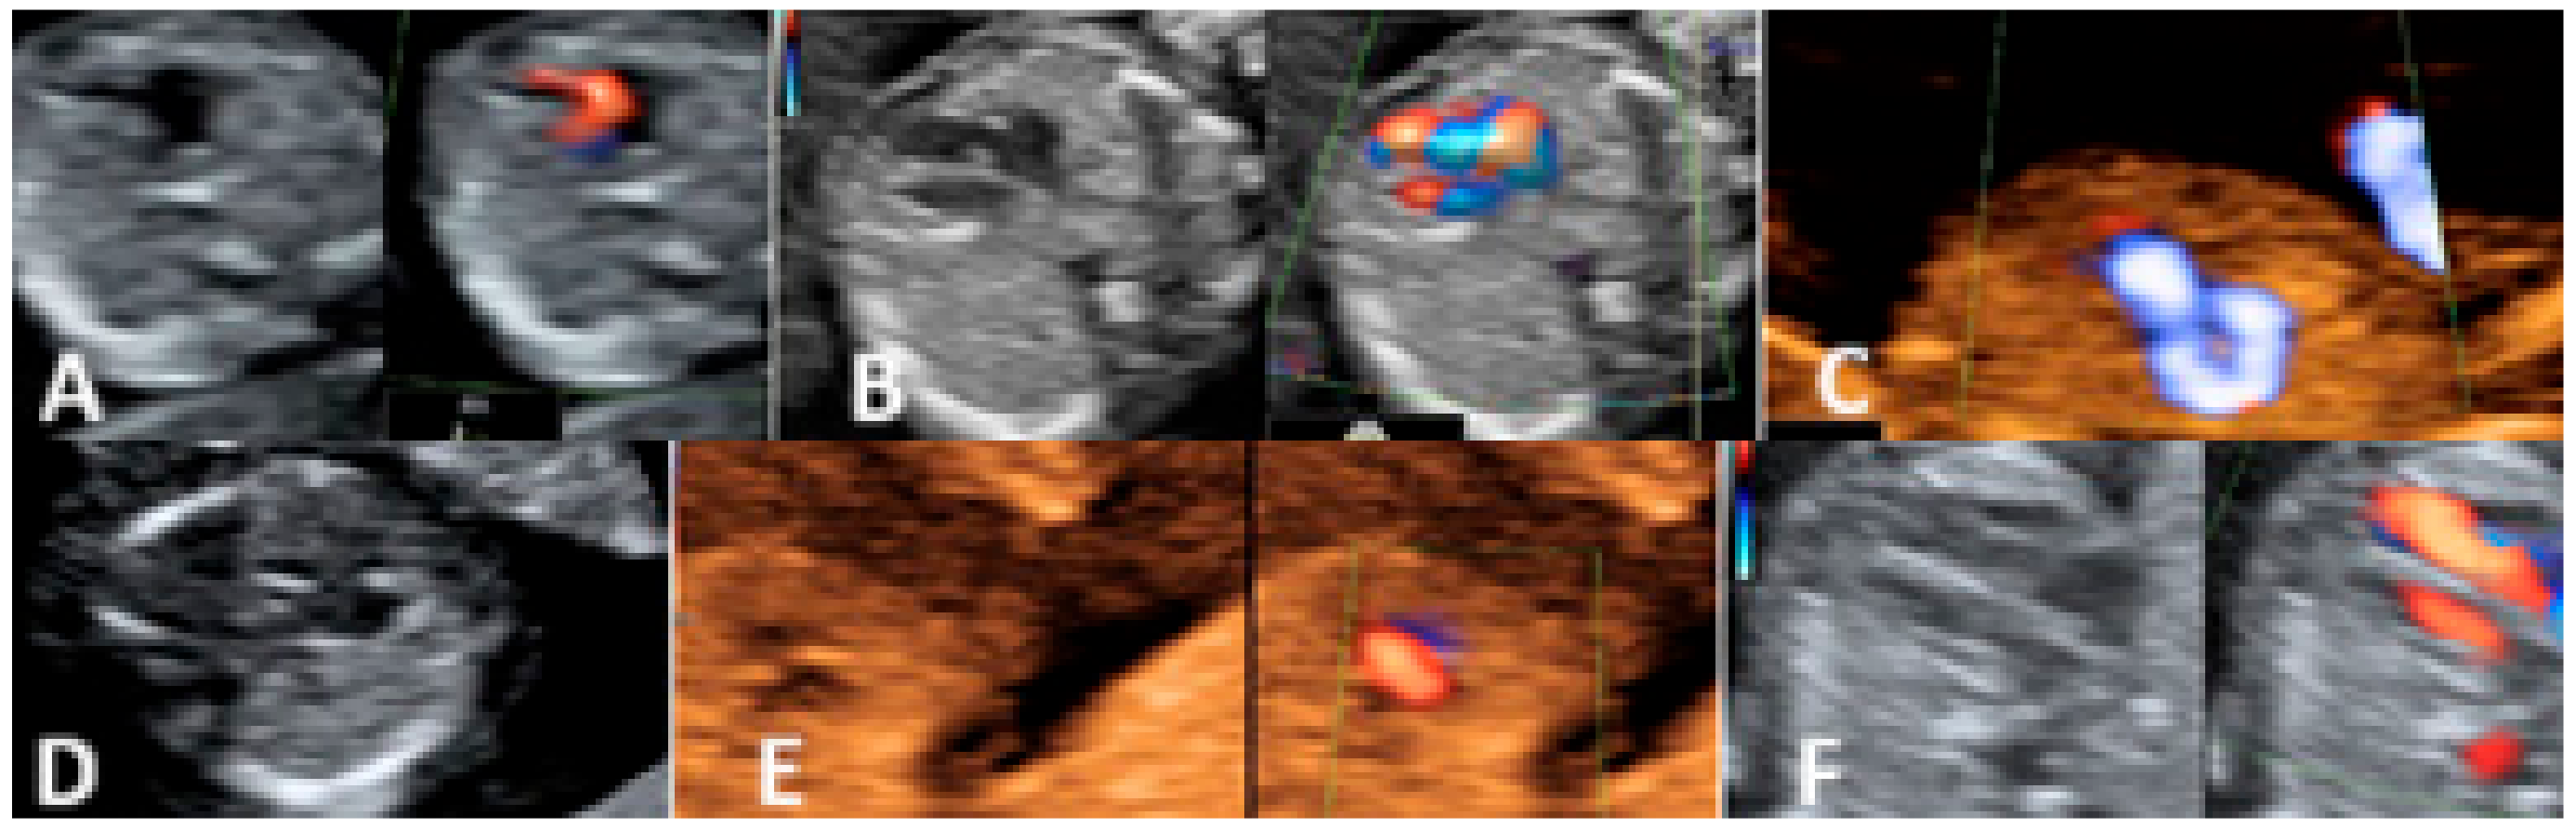

3.2. Second-Trimester Evaluation

| Tetralogy of Fallot | 3 | 3/17 (17.65%) | ||

| Membranous VSD | 5 | 5/17 (29.41%) | ||

| Supraventricular tachycardia (SVT) | 2 | 2/17 (11.76%) | ||

| Coarctation of the aorta | 3 | 3/17 (17.65%) | ||

| L-transposition of large vessels | 1 | 1/17 (5.88%) | ||

| Cardiomegaly due to aneurysm of the vein of Galen | 1 | 1/17 (5.88%) | ||

| Rhabdomyoma | 1 | 1/17 (5.88%) | ||